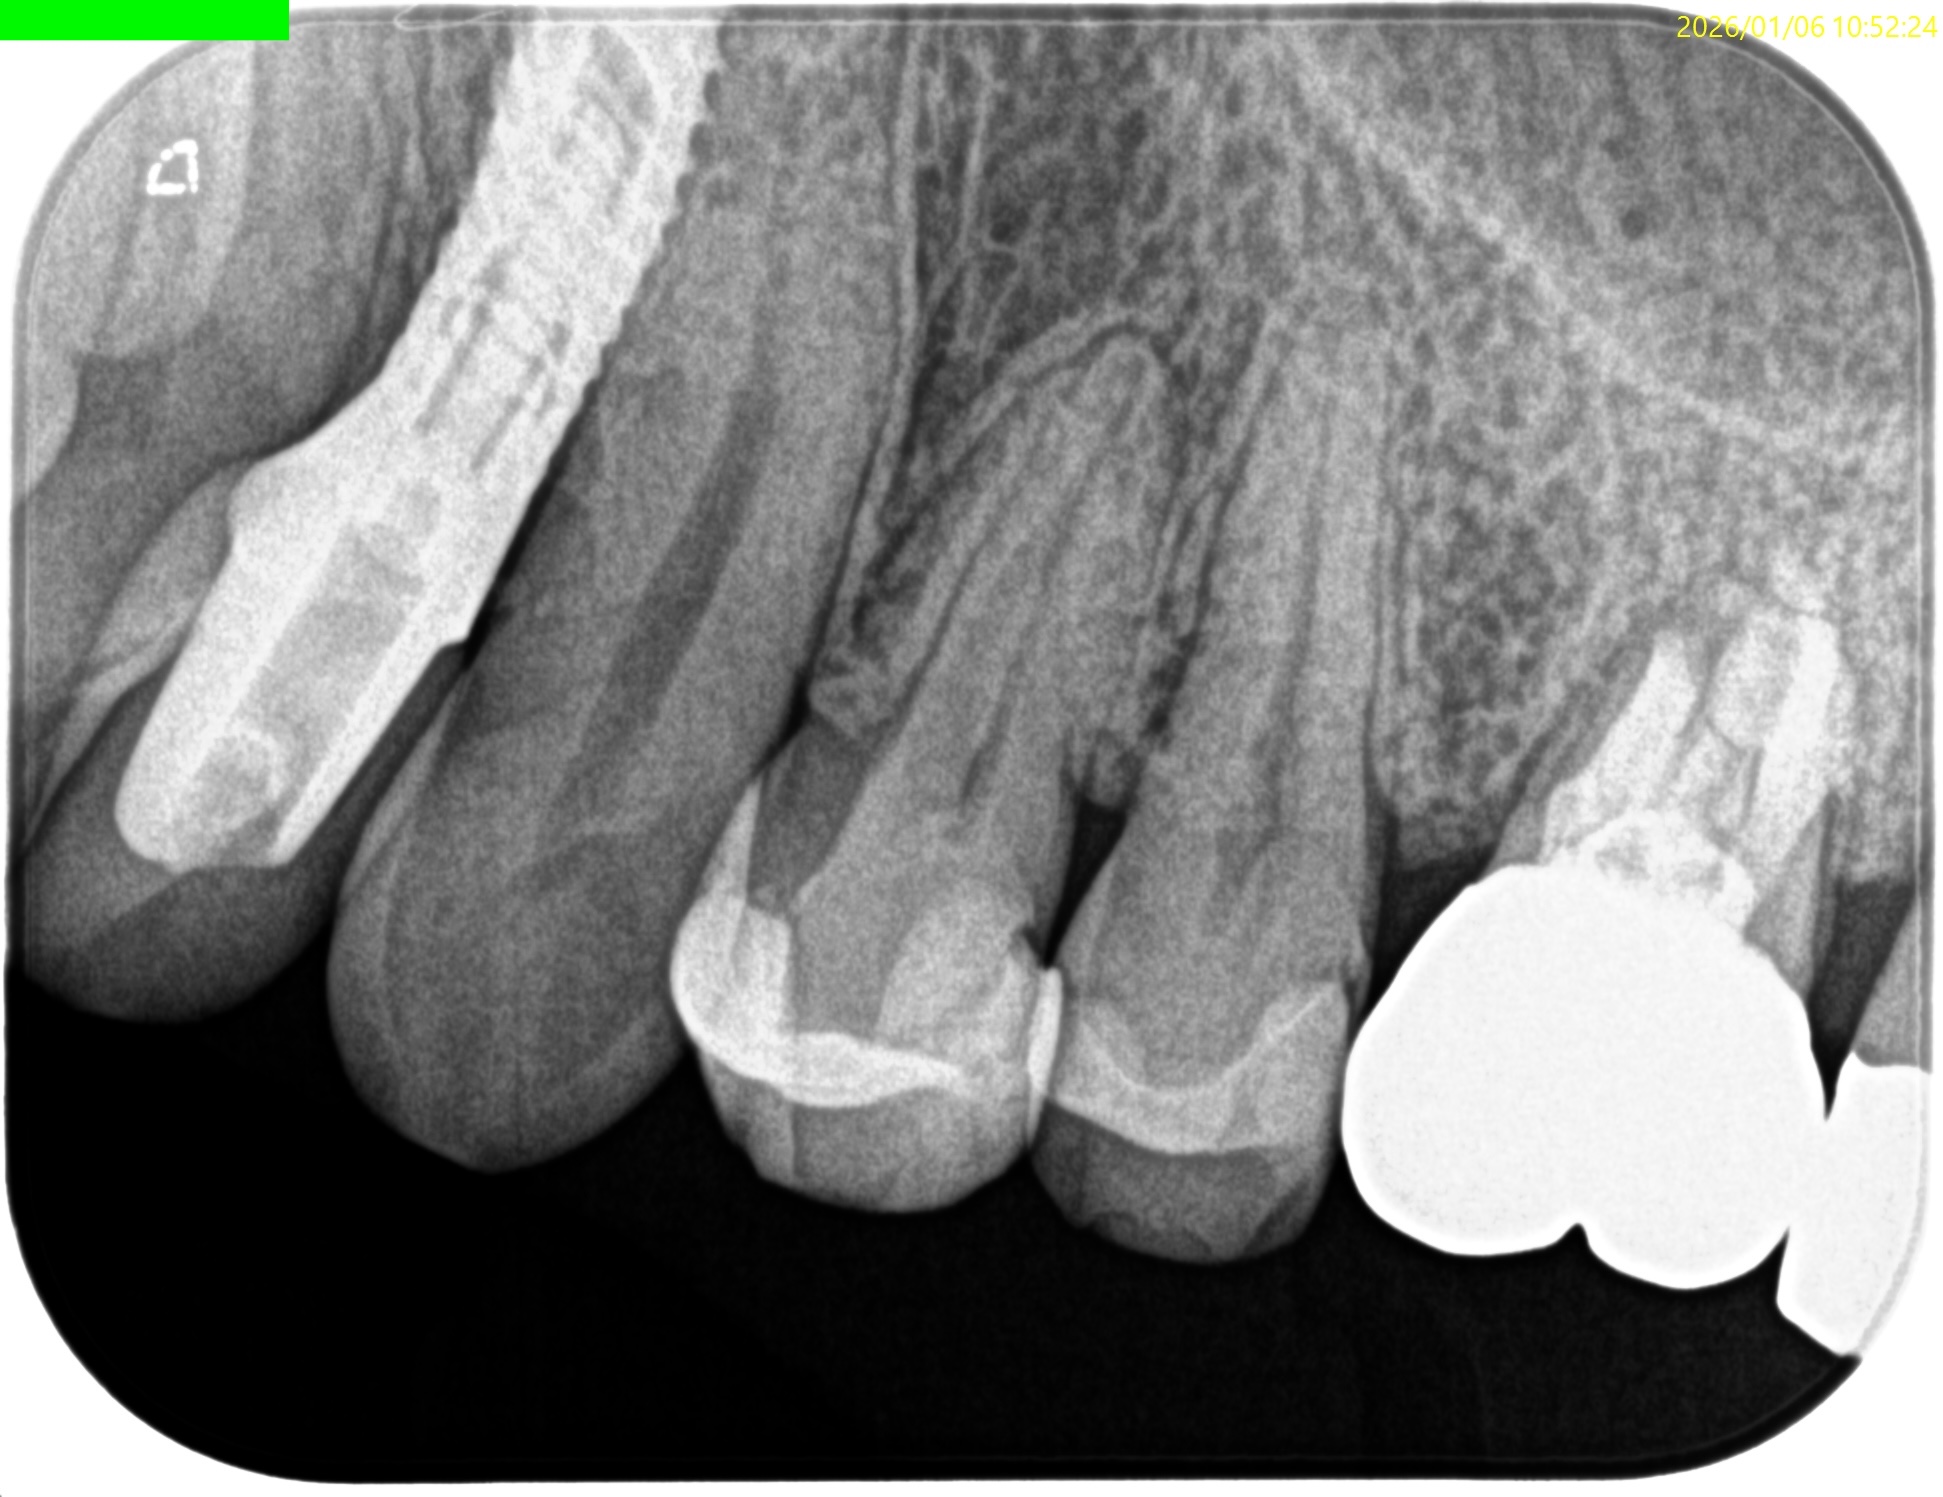

PA(2026.1.6)

Inlay除去後のCR修復は適合がいいとは決していえない感じだ。

2根管性で非機能咬頭のBが直線根管だ。

直覆のような処置がなされた形跡がある。

成人での直覆の成功率は低いことがすでにわかっていることから臨床症状と相まって#12 RCTが主訴の解決に寄与する可能性が高いだろう。